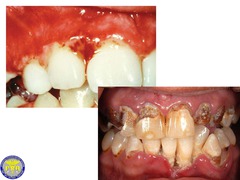

Meth mouth

Front

-generalized extensive destruction of tooth surface -meth use

erosion

-loss of tooth structure w/ smooth polished surface -cause: chemical action, bulemia